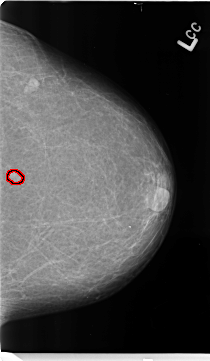

ics_version 1.0 filename B-3153-1 DATE_OF_STUDY 13 5 1998 PATIENT_AGE 69 FILM FILM_TYPE REGULAR DENSITY 1 DATE_DIGITIZED 21 4 1998 DIGITIZER LUMISYS LASER SEQUENCE LEFT_CC LINES 4688 PIXELS_PER_LINE 2720 BITS_PER_PIXEL 12 RESOLUTION 50 OVERLAY LEFT_MLO LINES 4688 PIXELS_PER_LINE 2776 BITS_PER_PIXEL 12 RESOLUTION 50 OVERLAY RIGHT_CC LINES 4728 PIXELS_PER_LINE 2760 BITS_PER_PIXEL 12 RESOLUTION 50 NON_OVERLAY RIGHT_MLO LINES 4736 PIXELS_PER_LINE 2872 BITS_PER_PIXEL 12 RESOLUTION 50 NON_OVERLAY |

FILE: B_3153_1.LEFT_CC.OVERLAY TOTAL_ABNORMALITIES 1 ABNORMALITY 1 LESION_TYPE MASS SHAPE IRREGULAR MARGINS ILL_DEFINED ASSESSMENT 4 SUBTLETY 4 PATHOLOGY BENIGN TOTAL_OUTLINES 1 BOUNDARY |